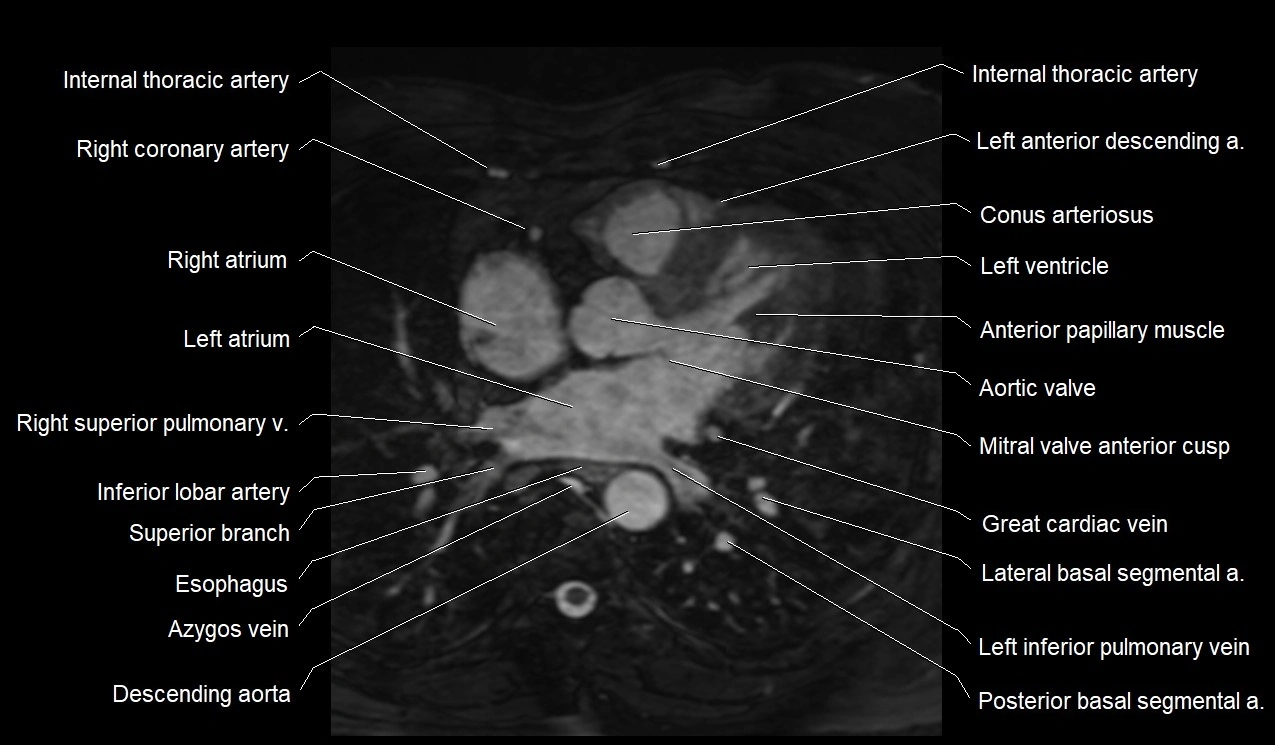

MRI image